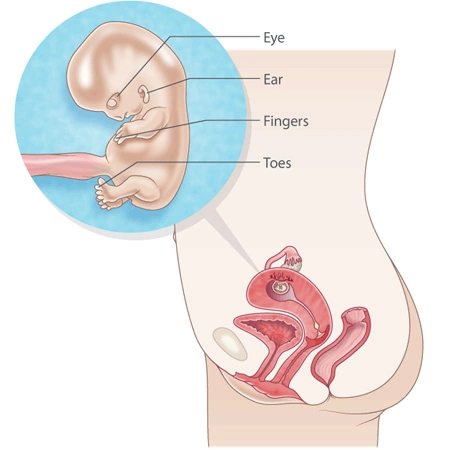

في الأسبوع العاشر من الحمل، لا يزال جنينك صغيراً، إلا أنه يخوض مرحلة نموّ سريع وواضح. إنه داخل السائل الأمنيوسي الدافئ والآمن، ويبلغ طوله حوالي ثلاثة سنتيمترات تقريباً. أصبح جسمه أكثر تناسباً— فلم يعد رأسه يبدو ضخماً مقارنة ببقية الجسم. تجوّفت مچاه وكواعبه، وأصابعه الصغيرة أصبحت واضحة للعين. إنّ تصور ذلك المخلوق الصغير الذي يكبر في داخلك يبعث شعوراً مدهشاً.

يمكن أن تكشف الأشعة فوق الصوتية أن الحويصلة الصفراوية (Yolk Sac) قد تراجعت، وأن الحبل السُري الذي يربط الجنين بالمشيمة أصبح واضحاً.

الأمعاء، التي كانت جزءاً من الحبل السُري، بدأت الانتقال إلى تجويف البطن وستُغطّى قريباً بالجلد.

يبدأ العديد من الأعضاء المهمة بوظائفها: الغدة الدرقية (Thyroid) أطلقت نشاطها، والبنكرياس يُنزل إنزيمات الهضم، والمرارة بدأت بإفراز الصفراء الضرورية لهضم الطعام بعد الولادة.

نسيج الرئتين يتكوَّن، كما بدأت العظام الصغيرة حتى في أصابع اليد والقدم بالظهور. الخلايا الموجودة بداخل هذه العظام ستصبح قريباً مسئولة عن إنتاج خلايا الدم الحمراء – وهي مهمة كانت حتى الآن تقع على الكبد والطحال.

ملامح الوجه أصبحت أكثر وضوحاً، وربما تكون البراعم الأولى لـ أسنان الحليب قد بدأت التكوّن. يستطيع الجنين الآن فتح فمه وتحريك لسانه، وإن كان لا يمكنه التلويح بعد!